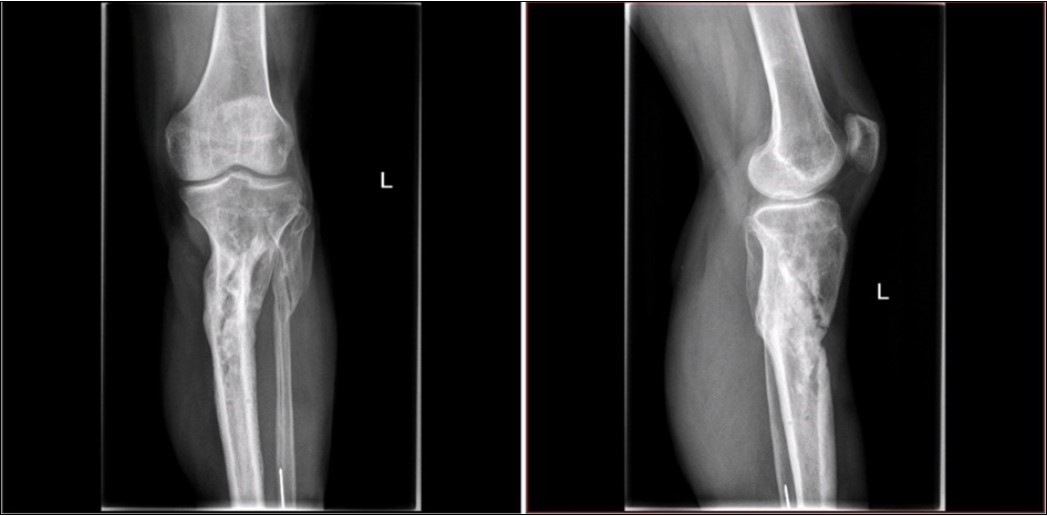

Figure 28.23 April. Surgery conversion of osteosynthesis. Removal external fixator and implantation intramedullary tibial nail. Gradual bone healing - last X-ray september 2019

Figure 29.23 April. Surgery conversion of osteosynthesis. Removal external fixator and implantation intramedullary tibial nail. Gradual bone healing - last X-ray september 2019